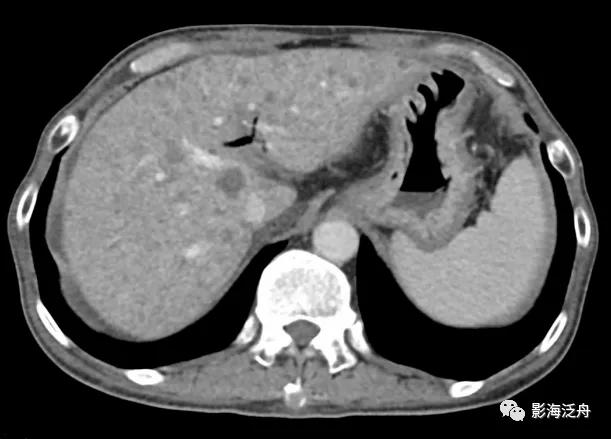

老年男性患者,因重度贫血就诊。

CT平扫上可见肝实质密度弥漫性增高,且明显高于同层面脾实质密度(黄箭),肝内血管呈较为明显的低密度改变(绿箭)。肝实质CT值75HU、脾实质CT值50HU。

同时需要注意的是肝实质密度增高≠肝内铁沉积,肝实质密度增高还见于结节病、Wilson病以及服用胺碘酮、甲氨蝶呤药物的患者。通常而言,肝实质密度在45~65HU之间,一般CT值大于或接近75HU可提示肝实质密度异常增高。